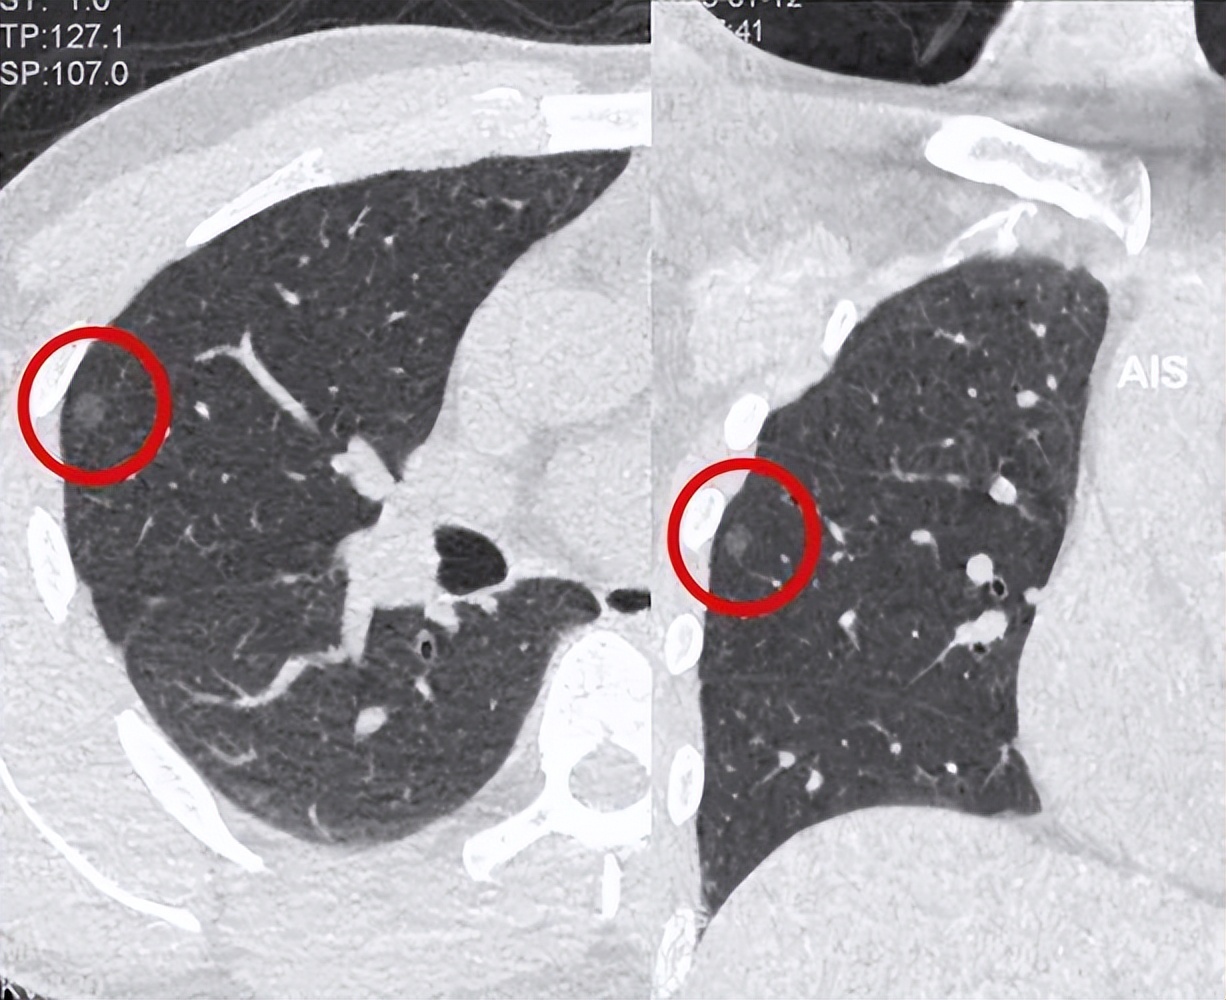

体检发现的肺结节并不一定是癌症,可能是炎症性或良性的肿瘤或结节。要确定肺结节的性质,一般需要通过以下检查:胸部CT、PET-CT、肺功能测试以及有时还需要进行肺活检或采用观察疗法。

肺结节的直径对其病理性质的判断很重要。一般规定,直径小于6毫米的结节具有很小的患肺癌风险;直径在6毫米以上,小于8-10毫米的结节可以按照个人情况进行检查和观察。

如果结节的直径大于10毫米,就需要重视了,需要进行进一步检查以确定它的病理性质。